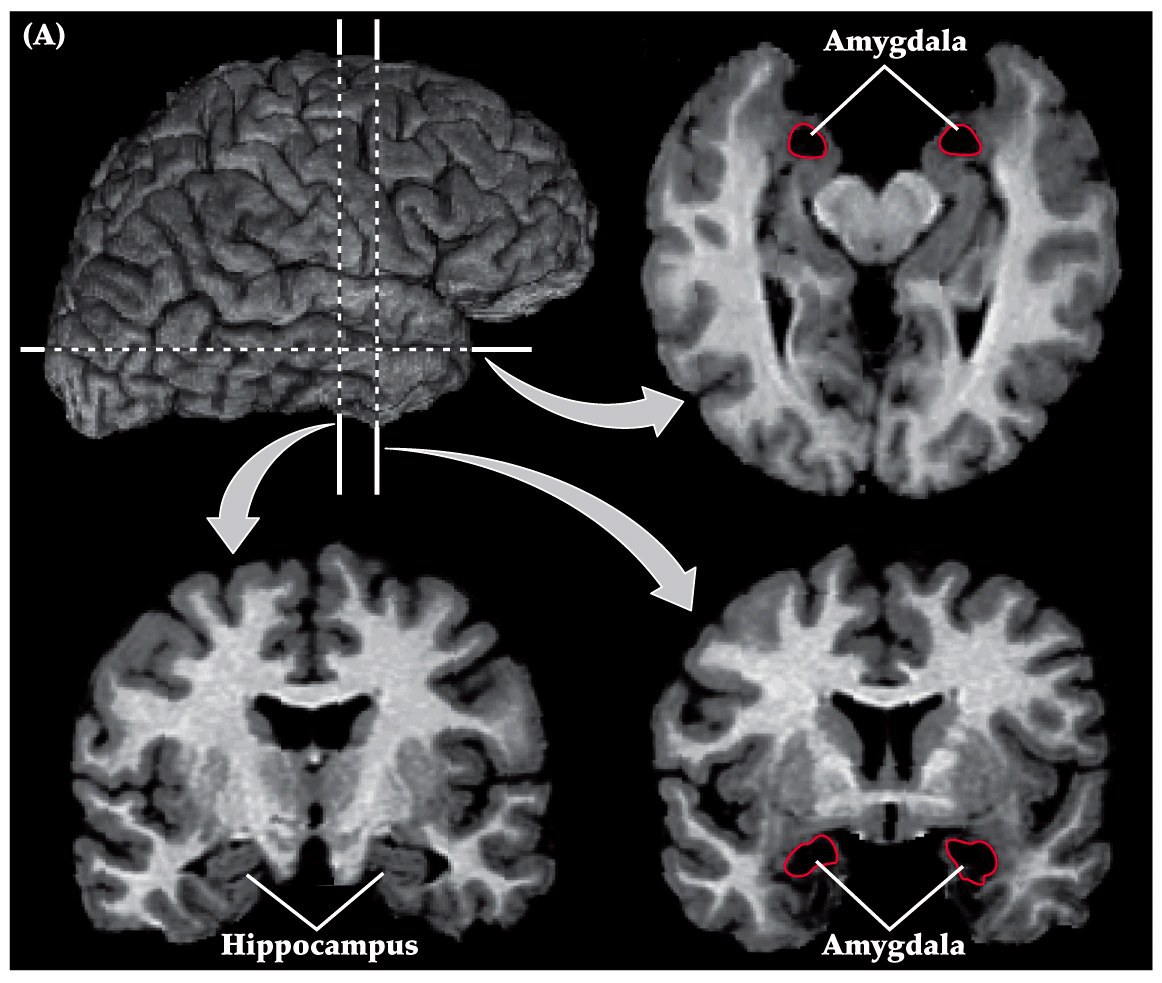

Amygdala

Neuroscience 5e Box 29B

• amgydala is in the anteior-medial part of the temporal lobe. Rostral to hippocampus

• three major functional and anatomical subdivisions

• medial group

• connections with olfactory bulb and olfactory cortex

• basal-lateral group

• large in humans

• major connections to orbital and medial prefrontal cortex of frontal lobe and association cortex of anterior temporal lobe

• central and anterior group

• connections to hypothalamus and brainstem (visceral sensory structures like nucleus of solitary tract and parabrachial nucleus)

• hypothalamus receives unprocessed sensory inputs, amygdala receives processed sensory inputs (cortex and thalamus)

• highly complex stimuli often needed to evoke response in amygdala (e.g. facelike neurons)